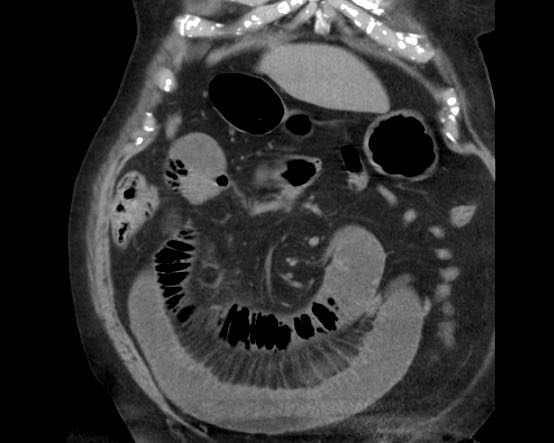

Đây là hình ảnh điển hình của tắc ruột do sỏi mật.

Lưu ý mức độ khó khăn khi phát hiện viên sỏi không vôi hóa.